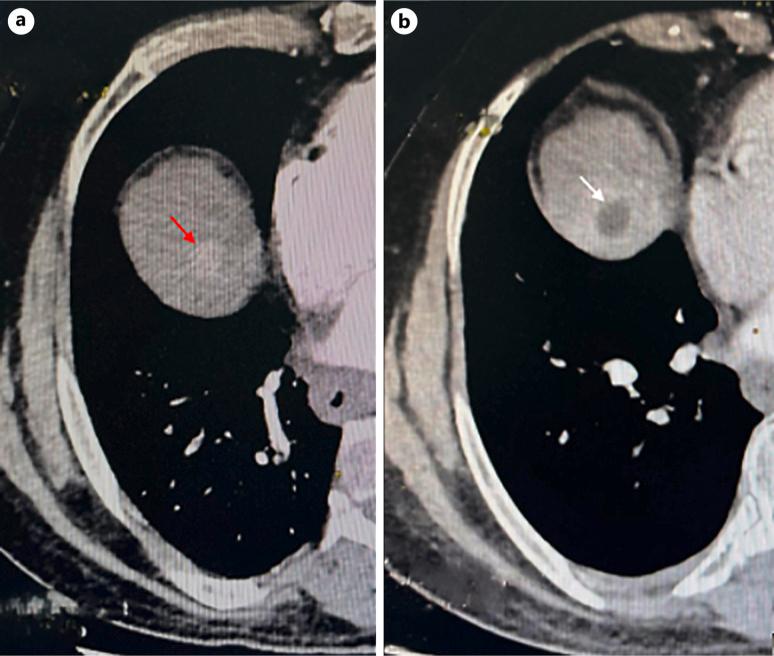

A 63-year-old male with compensated hepatitis B-related cirrhosis was under routine surveillance when a suspicious liver lesion was detected on ultrasound. Subsequent contrast-enhanced computed tomography (CT) confirmed the presence of an 18-mm HCC in segment VIII, corresponding to Barcelona Clinical Liver Cancer stage A. Due to limited curative treatment options, transarterial chemoembolization was considered. However, a follow-up CT scan was performed 2 weeks before the procedure unexpectedly revealed complete regression of arterial enhancement, suggestive of spontaneous tumor necrosis. The patient remained asymptomatic, with stable liver function and mild biological inflammatory markers. No evidence of vascular thrombosis or significant systemic inflammation was noted, suggesting localized vascular disturbances or intrinsic tumor factors might have precipitated the necrosis.

一名63岁的男性,患有代偿性乙型肝炎相关肝硬化,在常规监测期间,超声检查发现肝脏有可疑病变。随后的对比增强计算机断层扫描(CT)证实肝VIII段存在一个18毫米的HCC,符合巴塞罗那临床肝癌分期A期。由于根治性治疗选择有限,考虑进行经动脉化疗栓塞术。然而,在手术前2周进行的一次随访CT扫描意外显示动脉强化完全消退,提示肿瘤自发性坏死。患者仍无症状,肝功能稳定,生物炎症指标轻度升高。未发现血管血栓形成或明显全身炎症的证据,提示局部血管紊乱或肿瘤内在因素可能促成了坏死。